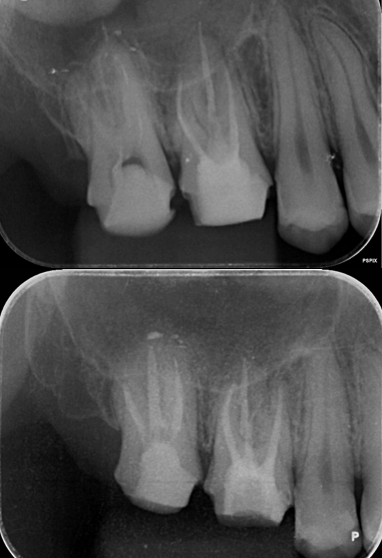

【グランドメゾンデンタルクリニック】抜歯後の骨...